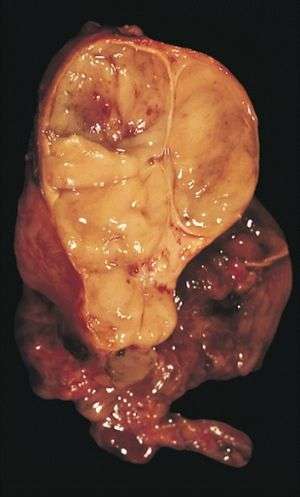

| An encapsulated thymoma (mixed lymphocytic and epithelial type) | |

An encapsulated cystic thymoma.